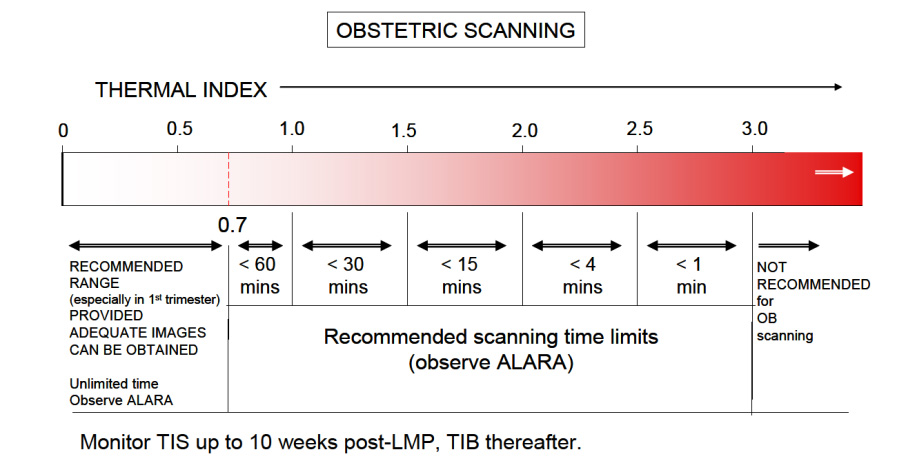

The Thermal Index is another safety metric which lets the operator know the potential of creating heat (hyperthermia) with the ultrasound beam. Many assumptions are made in this calculation, and it is often thought that the heating potential is underestimated. So keep in mind that the TI formulation was not intended to, and cannot provide an accurate measure of temperature rise within a specific patient. Instead it was designed to provide the operator with a relative measure of risk for a particular imaging mode. A Thermal Index of one (TI 1) indicates conditions under which the rise in temperature would be likely to be 1°C. The thermal index is different for different types of tissue, and can be displayed on your system accordingly: soft tissue (TIs), bone (TIb) and cranium (TIc). In the first trimester, when using Doppler to hear and demonstrate the fetal heart, the TIs setting us used. The limit for TI varies with time, please reference the chart below from the British Medical Ultrasound Society, the entire document may be found here.

First is the AIUM ALARA policy2; which is an acronym for As Low As Reasonably Achievable. Simply translated, it means to keep the output power settings as low as possible, that still allows for adequate images. Most ultrasound systems can operate with output power settings at about 50% and still produce quite satisfactory OB images. Have your system presets adjusted so that when you are performing OB sonography both (abdominally and transvaginally), the output power settings are set low. You can always increase them if clinically necessary. And keep in mind that you can increase the gain to make your image brighter, as gain is just how well the system is "listening", it has no effect on the TI.

The second concern is time. Keep the overall examination as short as is reasonable. If using Doppler to allow Mom to hear her baby's heartbeat, depending upon your ceter's policy, keep the Doppler exposure to about 5-10 seconds. Know where to find the MI and TI displays on your system. If you don't know, consult your operator's manual or contact the manufacturer of your ultrasound system for more information.

Diagnostic ultrasound in obstetrics has been around for the better part of 40 years. To date, no one has been able to prove (and many have tried) that diagnostic ultrasound, when used prudently (MI,<1.0 and TI<0.7), has had any adverse effects developing fetuses; and this includes the limited use of Doppler in the first trimester "Thus far, there have been no significant thermal effects documented in humans and at this time the possibility of having all the factors present to is highly unlikely 3." However, it has been shown that aborting a living fetus is fatal, every time.